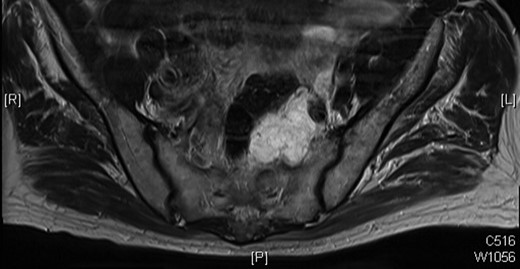

In July 2012, a follow-up MRI was done as surveillance for the mass, and this showed that the mass had extended into the left S1 neural foramen and another similar high signal area was seen to the left of the lower rectum and his CEA has continued to rise. After much discussion and in view of age and co-morbidity, together with the involvement of the pelvic sidewall, an R0 resection was not possible.

Given the extent of investigation to rule out another source of malignancy, the conclusion can be drawn that this is indeed a recurrence of the original villous adenoma that has undergone malignant change. This is a rare case that we believe is due to intra-operative seeding of tumour cells, as the original specimen was perforated. The time for malignant transformation from adenoma to carcinoma is indicative of the slow progression in some colorectal cancers [1, 2], presumably with mucin production (Figs 2 and 3). This case highlights the importance of obtaining a complete specimen with clear resection margins [3–5].

Progression of the mucinous mass on MRI in 2012. On repeated PET scanning, the mass shows minimal cellular activity.